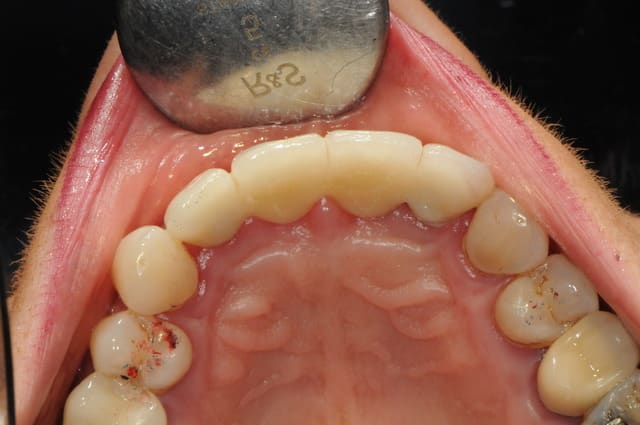

au mois d'octobre (j+5 mois), et malgré mon insistance, la patiente refusant de mettre en place les greffes muco-conjonctives pour récupérer le fiasco attendu sur 11, on débute la prothèse.

elle ne veut plus continuer, et sa reprise tabagique m'interdit une greffe. c'est vraiment dommage.

+ piliers et structure du bridge en zircone (j'adore mon proto)

+ piliers en place

+ mordu occlusale